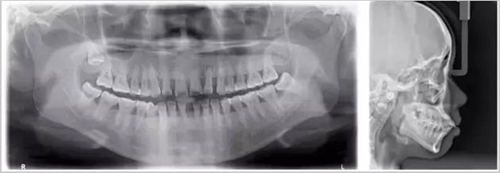

先放幾張圖,讓你們漲漲姿勢,不拍片根本不知道你的牙齒長得會有多奇葩!

從上圖中可以知道除了外層的一點牙釉質(zhì),牙齒里面出了問題,肉眼是無法觀察到的。牙醫(yī)不長透視眼當然不能透過現(xiàn)象看到牙齒本質(zhì)嘍。因此,為了對牙齒進行全面的了解,拍個牙片還是很有必要的。